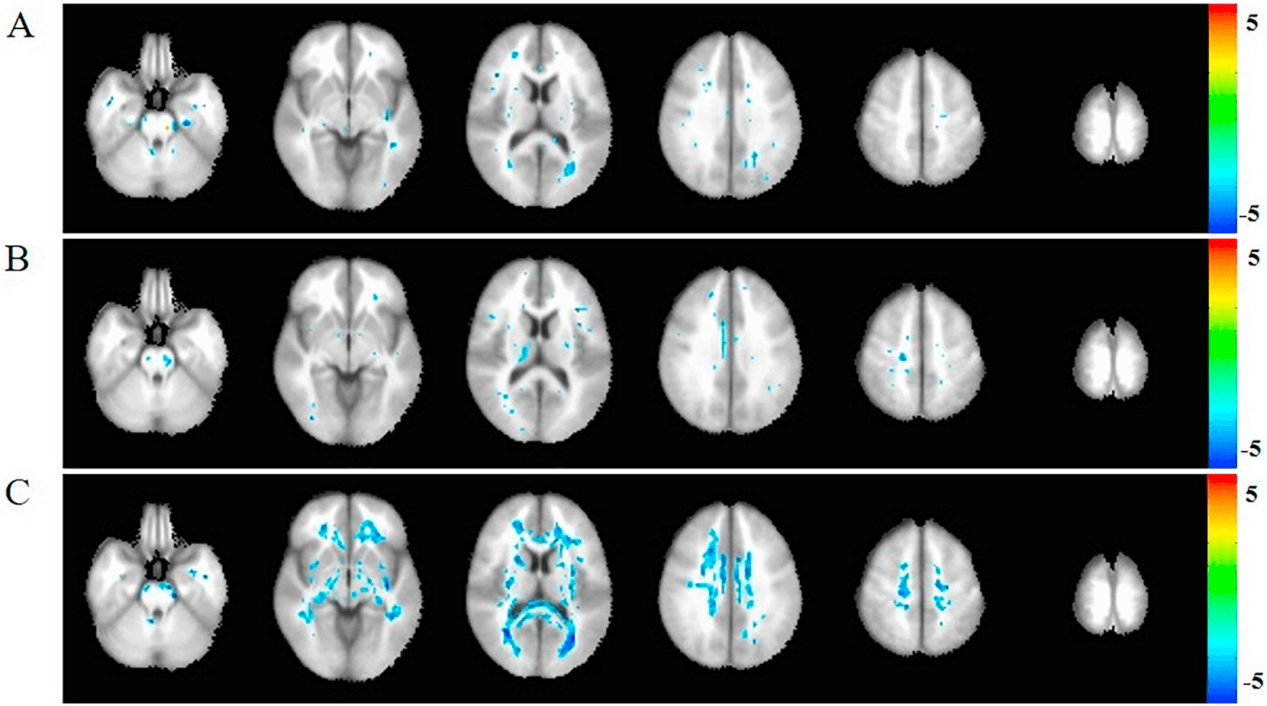

DKI数据分析系统

该系统提供完整的DKI数据预处理、基于体素的指标分析,以及基于白质骨架的跨组统计比较(TBSS)。同时,它支持基于DKI模型的确定性纤维追踪与结构网络构建,为研究脑肿瘤、神经退行性疾病等导致的复杂白质微结构变化提供了比传统DTI更具信息量的高级分析手段。